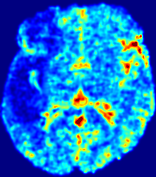

LesionRefer to captionRefer to captionRefer to captionRefer to captionRefer to captionRefer to caption𝐕rgbsubscript𝐕𝑟𝑔𝑏{\bf{V}}_{rgb}Refer to captionRefer to captionRefer to captionRefer to captionRefer to captionRefer to caption𝐕2subscriptnorm𝐕2{\|\bf{V}}\|_{2}Refer to captionRefer to captionRefer to captionRefer to captionRefer to captionRefer to captionRefer to caption3.53.53.52.82.82.82.12.12.11.41.41.40.70.70.70.00.00.0(mm/s)𝑚𝑚𝑠(mm/s)D𝐷DRefer to captionRefer to captionRefer to captionRefer to captionRefer to captionRefer to captionRefer to caption0.0200.0200.0200.0160.0160.0160.0120.0120.0120.0080.0080.0080.0040.0040.0040.0000.0000.000(mm2/s)𝑚superscript𝑚2𝑠(mm^{2}/s)Slice #1Slice #2Slice #3Slice #4Slice #5Slice #6

Figure 3: PIANO feature maps for one stroke patient, where the lesion is located in the left hemisphere. Top row: segmented stroke lesion region (white) on different slices, obtained from ISLES 2017. The corresponding slices for the PIANO feature maps are shown in the following rows.

For a better insight into an estimated velocity field 𝐕𝐕{\bf{V}} and diffusion field 𝐃𝐃{\bf{D}}, we compute the following maps: (1) 𝐕rgbsubscript𝐕𝑟𝑔𝑏{\bf{V}}_{rgb}: Color-coded orientation map of 𝐕=(Vx,Vy,Vz)T𝐕superscriptsuperscript𝑉𝑥superscript𝑉𝑦superscript𝑉𝑧𝑇{\bf{V}}=(V^{x},V^{y},V^{z})^{T}, obtained by normalizing 𝐕𝐕{\bf{V}} to unit length and mapping its 3 components to red, green, blue respectively; (2) 𝐕2subscriptnorm𝐕2\|{\bf{V}}\|_{2}: 222 norm of 𝐕𝐕{\bf{V}}; (3) D𝐷D: scalar field in Eq. 5.

Fig. 3 and Fig. 4 show the PIANO feature maps estimated from two ISLES 2017 patients: all are highly consistent with the lesion in both cases. Details of the blood flow trajectories are revealed in 𝐕rgbsubscript𝐕𝑟𝑔𝑏{\bf{V}}_{rgb} by the ridged patterns and the sharp changes of colors in the unaffected (right) hemisphere, while the flat patterns appearing within the lesion provide little directional information about the velocity and indicate low velocity magnitudes. Velocity magnitudes are more directly visualized via 𝐕2subscriptnorm𝐕2\|{\bf{V}}\|_{2}, from which one can easily locate the lesion where 𝐕2subscriptnorm𝐕2\|{\bf{V}}\|_{2} is low. D𝐷D also indicates lower diffusion values in the lesion, though with less contrast potentially due to the fact that it captures the accumulated effect of CA diffusion at the voxel-level.